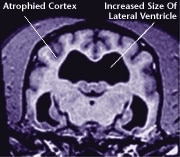

![]() Healthy Older Brain | ![]() Older Brain with Damage |

| MRI scans show loss of brain tissue in affected dogs. Note: MRI scans are not harmful to dogs. | |

Older, compromised mitochondria produce less energy and more highly toxic free radicals